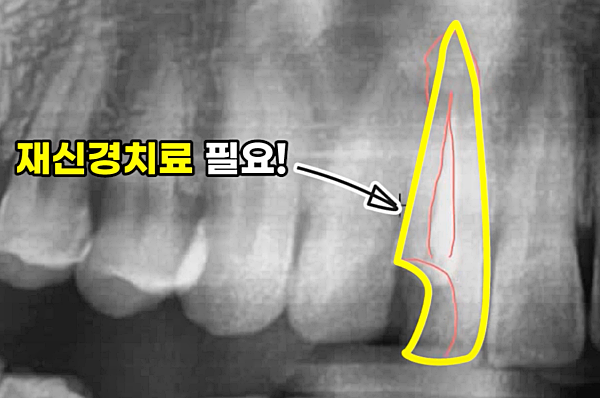

욱신욱신, 찌릿찌릿!! 분명 신경치료를 받고 왔는데 왜 치아 통증이 사라지지 않을까요? 고기를 좋아하는 음식물이 치아에 많이 끼는 편이에요. 그래서인지.... 최근 신경치료했던 부위의 치아와 잇몸에서 통증을 자주 느끼고 있었어요. 치과에 문의해 봤더니, 재신경치료가 필요할 수도 있다고 하셨어요. 이게 웬 날벼락! 신경치료가 얼마나 불편했는지 기억이 나면서 꼭 신경치료를 다시 해야 하는지 궁금하기 시작했습니다.

- 미세한 신경관까지 완벽히 신경이 제거되지 않은 경우: 복잡한 치아 신경관 구조 때문에 꼼꼼하게 제거하기 쉽지 않아 염증이 재발할 수 있습니다.

- 신경치료 후 시간이 지나면서 충전재에 미세한 틈이 있는 경우: 아무리 꼼꼼하게 밀봉해도 시간이 지나면서 충전재에 미세한 틈이 생길 수 있으며, 이 틈으로 세균이 침투하여 염증을 일으킬 수 있습니다.